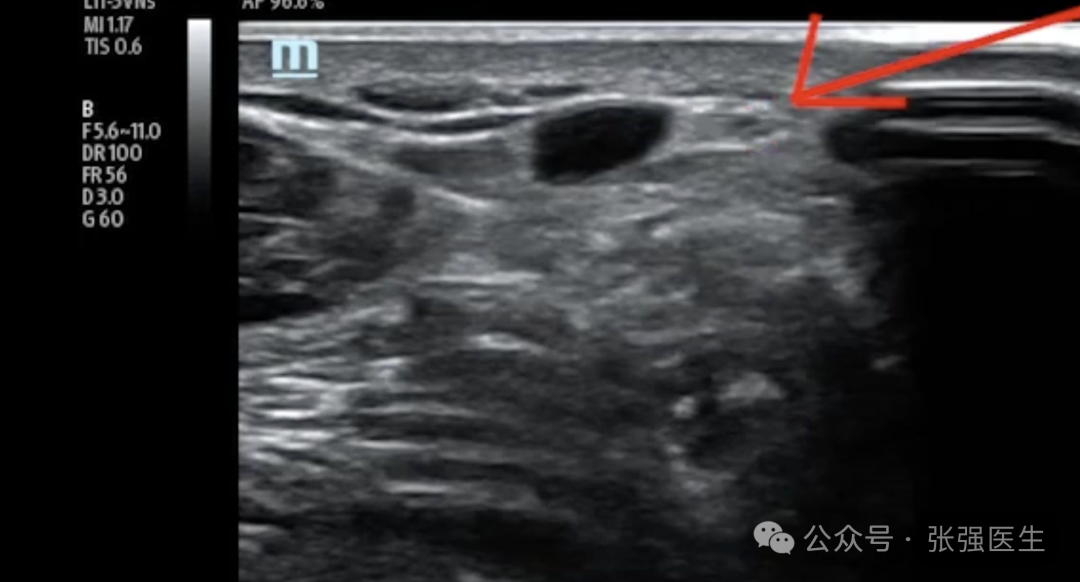

小隐静脉并不是一条孤立存在的血管,它与腓肠神经(sural nerve)伴行,在腘窝区域又与胫神经(tibial nerve)关系密切。

小隐静脉与腓肠神经在多数情况下的距离小于5 mm;在腘窝区(SPJ),与胫神经的平均距离约为4.4 mm,部分个体甚至小于1 mm;同时,在小腿远端约三分之二的区域,深筋膜常缺失或不连续,缺乏有效的解剖隔离。

这一系列结构特征共同决定了:在小隐静脉系统中,静脉与神经并非简单相邻,而是处于高度共存的状态。